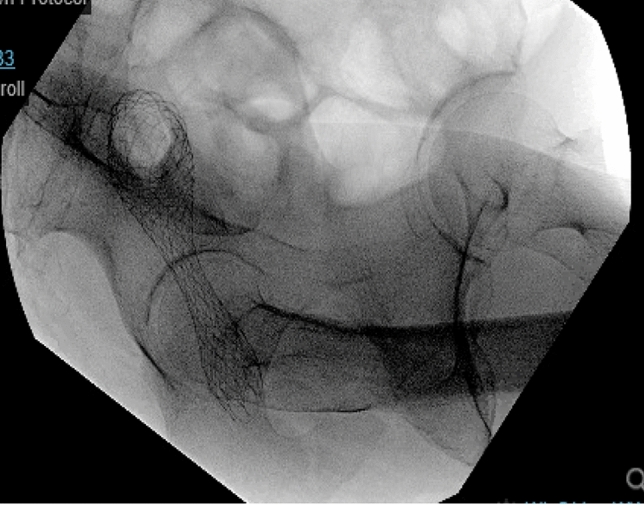

Methods: We present a 72-year-old male with prior radical cystectomy and neobladder creation complicated at the time by neobladder-cutaneous fistula and wound infection requiring revisional surgery and incisional hernia repair with mesh. He developed a large recurrent incisional hernia and underwent open hernia repair with bilateral anterior component separation, extensive lysis of adhesions, removal of prior mesh, and placement of a biologic mesh (Strattice™ RTM) in an underlay and onlay fashion. Intraoperatively, the defect measured 20 cm long by 14 cm wide. Postoperatively, he was treated for neobladder infection and CT cystogram found no extravasation from the neobladder. He presented to the emergency department 6 weeks after surgery with spontaneous partial midline wound dehiscence, with exposure of the onlay mesh and drainage of clear fluid, which was confirmed to be urine by fluid creatinine level. Repeat CT scan demonstrated a filling defect at the anterior wall of the neobladder with contrast leaking into a contained collection interposed between the anterior abdominal wall and the underlay mesh, extending superiorly between the small bowel loops and dehiscence of the midline abdominal wound. The patient was treated with a course of antibiotics and indwelling Foley catheter and bilateral nephrostomy tubes for urine diversion.

Results: Three months later, repeat CT cystogram demonstrated resolution of the leak and the nephrostomy tubes and Foley catheter were removed. The patient has continued daily wound care with significant reduction in size of the midline wound and increasing granulation tissue around the onlay mesh. He has not required further admissions to hospital and there has been no hernia recurrence so far.